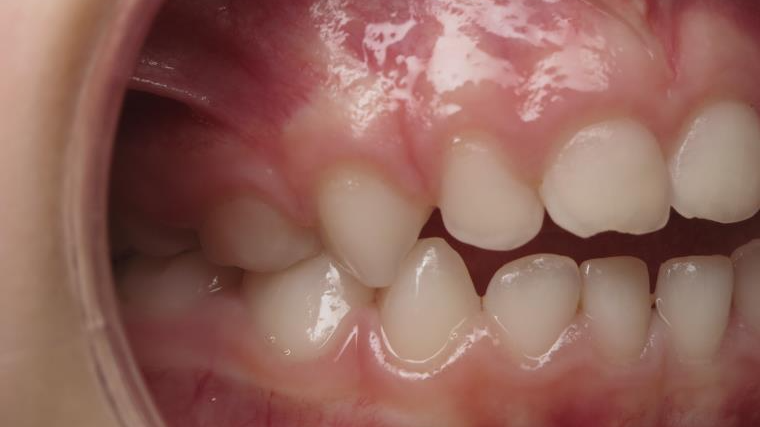

inversion postérieur coté droit et espace entre l'arcade du haut et du bas (béance)

appareillage mobile pendant 5 mois